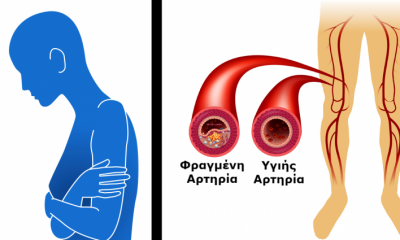

8 Σημάδια-καμπανάκια που μας Προειδοποιούν ότι έχουμε Φραγμένες αρτηρίες και ΔΕΝ Πρέπει να Αγνοήσουμε!

19 Σεπτεμβρίου 2018Κουράζεστε εύκολα και παθαίνετε κράμπες στα πόδια σας μετά από λίγη ώρα περπατήματος; Εάν ναι, τότε...